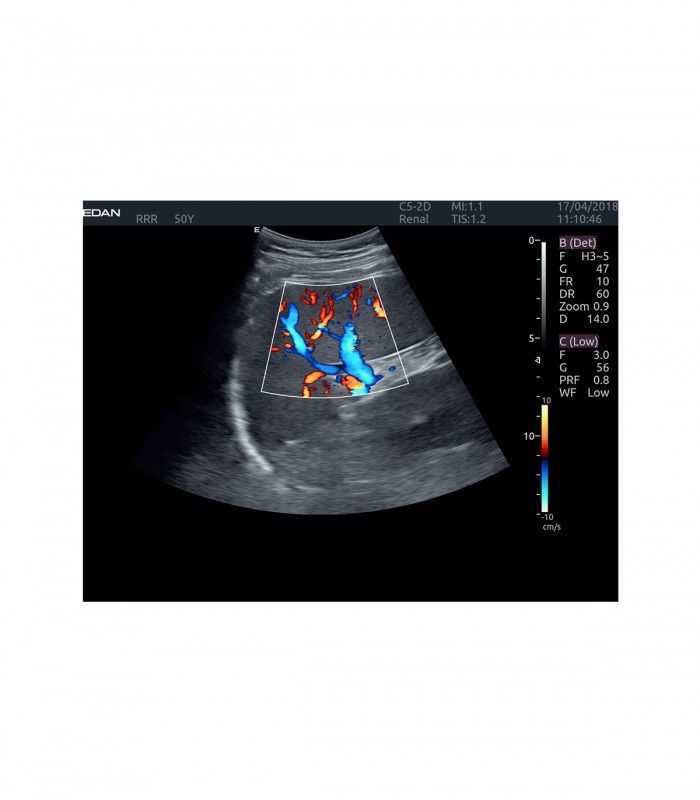

L’AX4 affiche une image claire et précise dans les différents modes grâce à de multiple technologies de traitement de l’image.

En mode couleur, les préréglages et le TAI automatique temps réel facilitent l’ajustement des flux.

- Imagerie entièrement automatisée (modes B, couleur, doppler, M)

- Dopplers pulsé PW, continu CW, énergie (ou puissance) PDI et DPDI